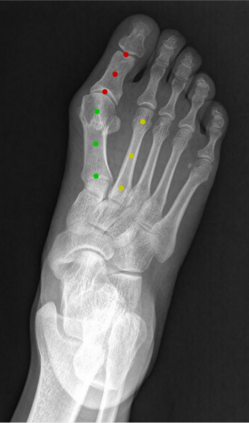

Angular measurements is essential to make a resonable treatment for Hallux valgus (HV), a common forefoot deformity. However, it still depends on manual labeling and measurement, which is time-consuming and sometimes unreliable. Automating this process is a thing of concern. However, it lack of dataset and the keypoints based method which made a great success in pose estimation is not suitable for this field.To solve the problems, we made a dataset and developed an algorithm based on deep learning and linear regression. It shows great fitting ability to the ground truth.